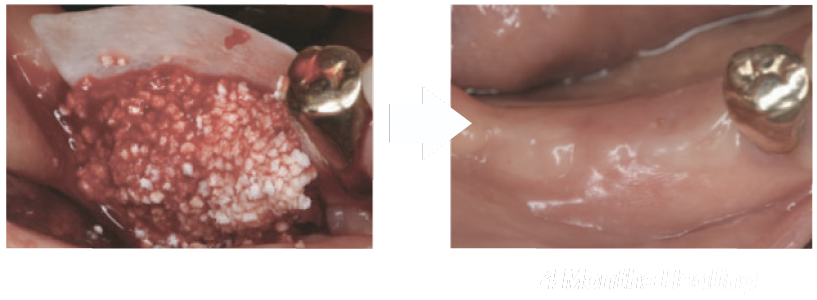

100% Synthetic bone grafting material

HA scaffold with β -TCP (HA 30% + β -TCP 70%).

Resorbable bone grafting material

which is ideal for socket preservation and implant site.

100% Synthetic bone grafting material

HA scaffold with β -TCP (HA 30% + β -TCP 70%).

Resorbable bone grafting material

which is ideal for socket preservation and implant site.